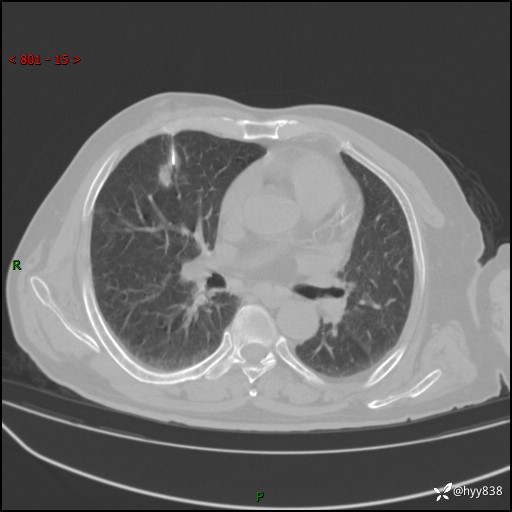

CT导向穿刺(靶点---2个结节)